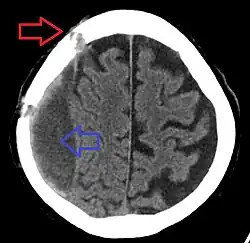

Chronic subdural after treatment with burr holes

A person must receive medical assessment, including a complete neurological examination, after any head trauma. A CT scan or MRI scan will usually detect significant subdural hematomas.

Treatment of a subdural hematoma depends on its size and rate of growth. Some small subdural hematomas can be managed by careful monitoring as the blood clot is eventually resorbed naturally. Others can be treated by inserting a small catheter through a hole drilled through the skull and sucking out the hematoma.

Large or symptomatic hematomas require a craniotomy. A surgeon opens the skull and then the dura mater; removes the clot with suction or irrigation; and identifies and controls sites of bleeding.[28][29] The injured vessels must be repaired. Postoperative complications can include increased intracranial pressure, brain edema, new or recurrent bleeding, infection, and seizures. In patients with a chronic subdural hematoma but no history of seizures, it is unclear whether anticonvulsants are harmful or beneficial.[30]